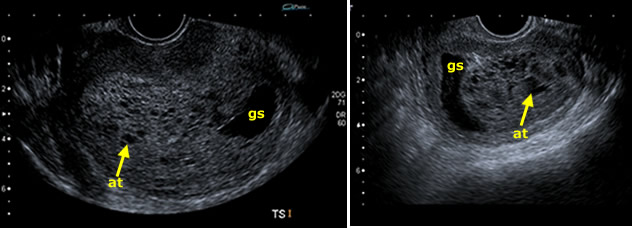

Opposite are shown the two ultrasound scans taken in the midline of the pelvis.

C. Correct. There is a small gestation sac, although it is difficult to see an embryo. The trophoblast/placenta is, however enlarged and heterogeneous, containing many black cystic spaces. Although similar appearances may be seen in hydropic change of a missed miscarriage, the changes are very pronounced and suggest a molar pregnancy. This is a partial mole (see image below).

gs = gestation sac; at = abnormal trophoblast